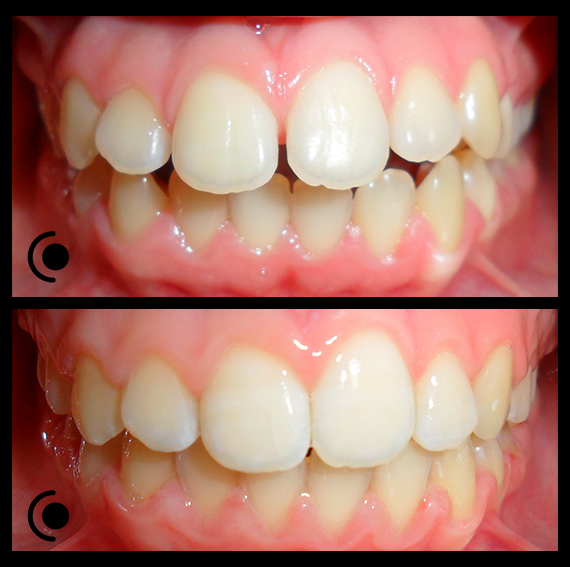

O našoj kvaliteti najbolje govore naši rezultati!

Centar za ortodonciju Petra Džapo